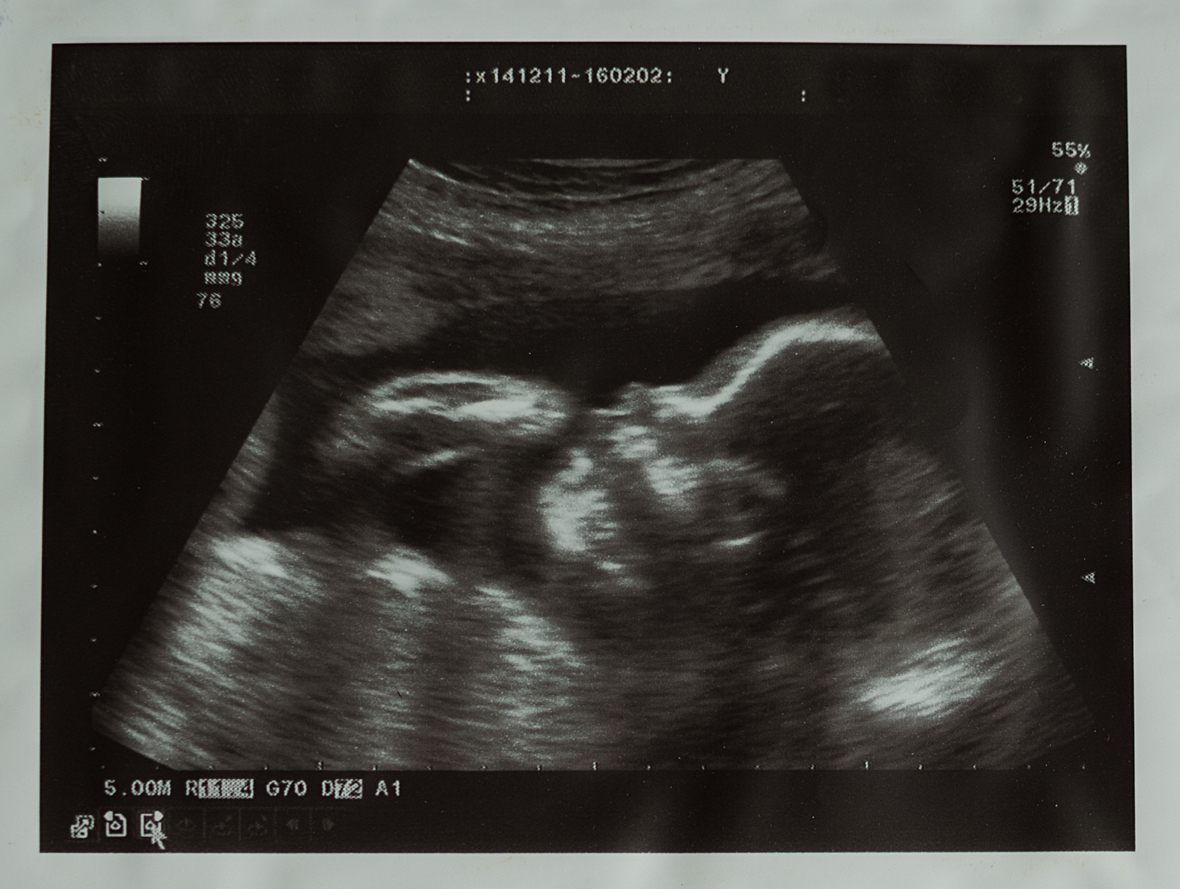

Плод на 13 акушерской неделе. УЗИ и обследование

13 недель беременности — самое подходящее время для проведения первого скринингового УЗИ! Если вы не провели это исследование на 11–12 неделе, желательно без отлагательств отправиться к доктору и получить направление на процедуру.

На сроке 13 недель ультразвуковое исследование считается безвредным; даже напротив, если до этого процедура не проводилась, ее очень важно сделать до 14-ой недели, чтобы выявить некоторые нарушения, которые потом будут не видны.

На 13 неделях ультразвуковое исследование обычно проводится трансабдоминальным способом, то есть, через кожу живота. На живот наносится небольшое количество специального геля, и врач начинает перемещать датчик по поверхности кожи, разглядывая малыша (краем глаза весь этот процесс можете видеть и вы) и сообщая медсестре, заполняющей заключение к процедуре, изученные параметры.

Все это, как правило, длится порядка 10 минут, после чего будущей маме разрешают стереть с живота гель, встать и одеться. Впрочем, мы пропустили один момент: как правило, особенно, если процедура проводится не в консультации, где за дверьми кабинета стоит огромная очередь, а в частной клинике, напоследок женщине тоже демонстрируют монитор и показывают очертания ребенка, чтобы она могла хорошо его рассмотреть.

Во время этого УЗИ проводится осмотр матки и ее содержимого, визуализируются все органы и оцениваются особые параметры, изменение которых предполагает возможное наличие пороков развития (в частности, воротниковое пространство).

УЗИ на указанном сроке еще иногда называют «генетическим», так как главной его целью является определение признаков аномалий развития и хромосомных заболеваний у ребенка. Конечно, стоит отметить, что исследование не позволяет 100% утверждать наличие той или иной патологии, врач может по совокупности признаков лишь предположить наличие заболевания, после чего женщину отправляют к генетику, который точнее определяет риск рождения ребенка с серьезной патологией.

При проведении УЗИ на 13 неделе беременности КТР уже не выполняет информативную функцию. Состояние малыша определяется по:

- окружности живота;

- длине бедренной кости;

- бипариетальному размеру.